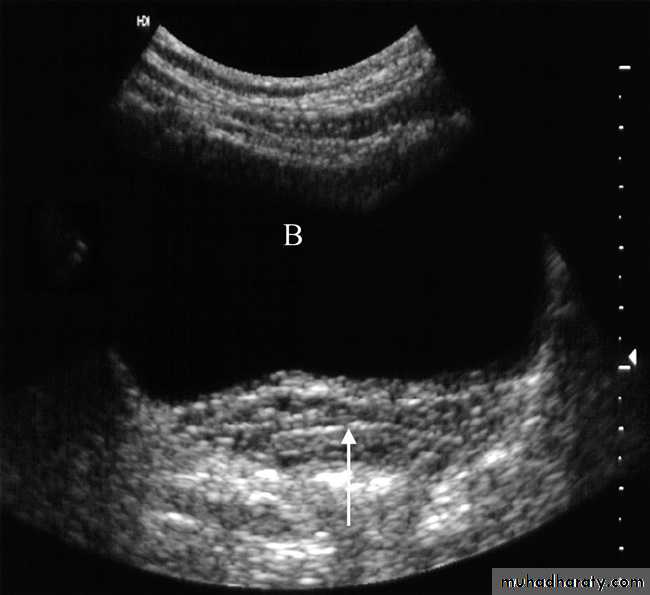

The urinary bladder should be examined in the distended state: the walls should be sharply defined and barely perceptible .The bladder may also be assessed following micturition, to measure the post micturition residual volume of urine.Urography